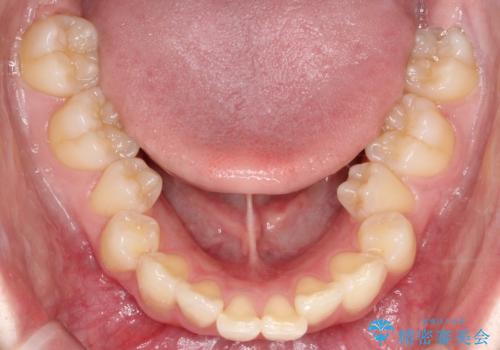

- 前歯が突き出ていることによる口元の突出感と、下顎が右側にズレていること(右方偏位)を主訴にご来院されました。

精密検査の結果、歯を並べるスペースの不足に加え、上下の歯列の正中(中心)が大きくズレていることが確認されました。突出した口元を下げ、顎の左右バランスを整えるためのスペースを確保するため、右上・左上・左下の4番目(第一小臼歯)を計3本抜歯する計画を立案。装置は、治療中の見た目にも配慮し、目立ちにくい審美ワイヤーを選択しました。

治療は、抜歯によって得られたスペースを活用し、前歯を後方へ移動させながら上下の中心を一致させる緻密な調整を行いました。

特に下顎の右方偏位に対しては、ワイヤーによる繊細なコントロールを行い、左右の咬合バランスを整えることに重点を置きました。2年半の治療期間を経て、突出していた前歯は理想的な位置に収まり、顎のズレも大幅に改善されました。